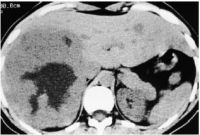

2.CT扫描:海绵状血管瘤CT平扫表现为低密度,且密度均匀,大的血管瘤病灶中央可见更低密度区,呈星形、裂隙状或不规则形。瘤内偶见钙化,呈圆形或不定形强回声,病灶边缘通常清晰光滑。典型者增强扫描表现为早期病灶边缘呈高密度强化,随后增强区进行性向中心扩展,延迟扫描病灶呈等密度充填,显示“快进慢出”的表现。直径小于3cm的血管瘤增强扫描表现较为复杂,可有以下表现:病灶早期呈高密度强化,也有的病灶强化不显著,低于正常肝组织,延迟扫描所有病灶均呈等密度充填。个别病例始终无强化,延迟扫描也无充填,此类血管瘤管壁很厚,管腔狭小,造影剂难以进入。

肝海绵状血管瘤